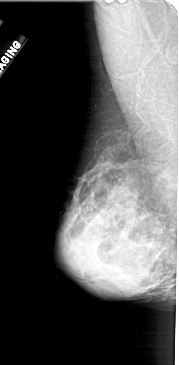

A_1570_1.LEFT_MLO

LEFT_MLO LINES 5101 PIXELS_PER_LINE 2506 BITS_PER_PIXEL 12 RESOLUTION 43.5 NON_OVERLAY